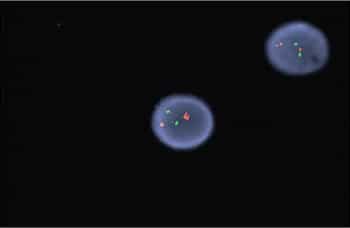

Case. A 16-year-old male presented with a one-week history of fatigue and easy bruising. Complete blood count revealed a white count of 4.8 × 103/mm3 with left shift of the myeloid lineage with 50 percent blasts, hematocrit of 31 percent, hemoglobin of 10.8 g/dL, and a platelet count of 29 × 103/mm3. Review of the peripheral blood smear showed numerous blasts with increased nuclear-cytoplasmic ratio and bilobed nuclei with sliding plate morphology (Fig. 2). Myeloperoxidase stain performed on the peripheral blood was strongly positive (Fig. 3). The morphologic and clinical findings were concerning for APL and thus the clinical team started ATRA (all-trans-retinoic acid) while awaiting final diagnosis. Flow cytometry revealed the blast population to be dim CD45, bright CD33, subset CD34, dim HLA-DR, dim CD13, CD117, subset CD56, and cytoplasmic MPO positive (Fig. 4). Dual color dual fusion fluorescence in situ hybridization was negative for t(15;17) (Fig. 5).6

A bone marrow biopsy was then performed and revealed a hypercellular marrow with left shifted maturation in the myeloid lineage with 77 percent blasts (Fig. 6). Blast morphology was similar to the peripheral blood. Flow cytometry performed on the bone marrow was identical to the peripheral blood. Conventional karyotype performed on the bone marrow revealed a normal male chromosome complement with no abnormalities identified. Due to the clinical suspicion of APL along with blast morphology and immunophenotype, despite negative FISH and karyotype, reverse transcription-polymerase chain reaction (RT-PCR) testing was obtained.7 Testing revealed a cryptic t(15;17) with the bcr-3 transcript, and the patient was formally diagnosed with APL (Fig. 7). Despite starting ATRA, the patient developed DIC, which was effectively treated with transfusion. The patient was discharged home one month later and remains in remission more than three years later.

Discussion. APL is an acute leukemia that is defined by t(15;17) and requires prompt diagnosis because it is associated with DIC. Review of blast morphology and cytochemical stains can aid the pathologist in narrowing the differential diagnosis, but the final diagnosis of APL often requires additional testing. It is common for rapid turnaround FISH to be performed to identify the t(15;17), thus securing the diagnosis. However, in cases such as this one, FISH and karyotype will fail to identify the cryptic translocation. Delay in diagnosis in these cases may be detrimental and even lead to death if ATRA therapy is not begun.

Cryptic translocations of APL account for about two percent to four percent of all APL cases. The majority of cryptic translocations result from submicroscopic insertions of RARA into PML, but complex rearrangements involving numerous chromosomes can also be a cause. In addition, variant translocations between RARA and other genes can occur. Variant translocations may require additional FISH probes as they may not be recognized by usual t(15;17) dual color probes; it is important to recognize, however, that these are not cryptic translocations but variant translocations. Furthermore, all cryptic and variant alterations involve RARA but may not involve PML, highlighting the importance of RARA gene alterations in the development of APL.

Although it may seem that the initial best option would be to use RT-PCR testing primarily, each testing modality has its own advantages. FISH carries the advantage of there being specific probes to detect the translocation and can often be completed within 24 hours. In addition, break-apart probes can be used to identify fusions with other partners, an advantage when dealing with variant translocations. The disadvantages of FISH are its insensitivity for minimal residual disease monitoring and the possibility of missing cryptic cases, such as this case. Conventional karyotype, with a longer turnaround time of five to 10 days, can identify the usual t(15;17) and may also identify other genetic abnormalities that have prognostic significance. Karyotype may also miss cryptic translocations and it too is insensitive to monitoring for minimal residual disease. RT-PCR is by far the most sensitive testing modality and is frequently used for minimal residual disease monitoring and to identify cryptic translocations. Turnaround time, however, is typically longer than for FISH. RT-PCR has the added advantage that it can identify the specific translocation subtype, including bcr-1, -2, or -3.